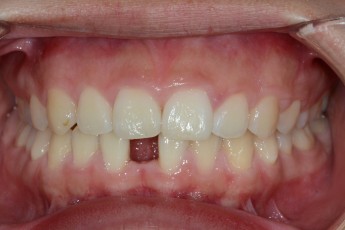

Before

After